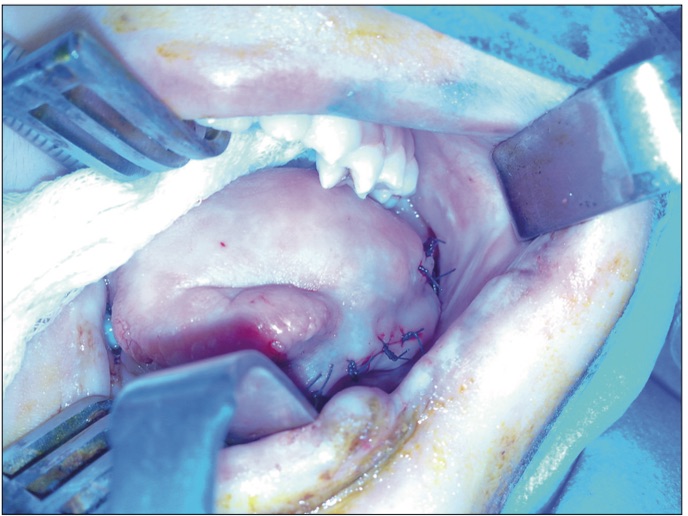

و أوضحت أنّ هذه التّقنية الجراحيّة تتمثّل في فتح القناة النّاقلة للّعاب، الواقعة تحت اللّسان، على الحلق ممّا يمكّن المريض من ابتلاع لعابه بطريقة طبيعيّة، و أنّ هذه التّقنية ناجعة و سليمة من المضار والمضاعفات، وأنّ عمليّة جراحيّة واحدة تكفي للعلاج النّهائي.